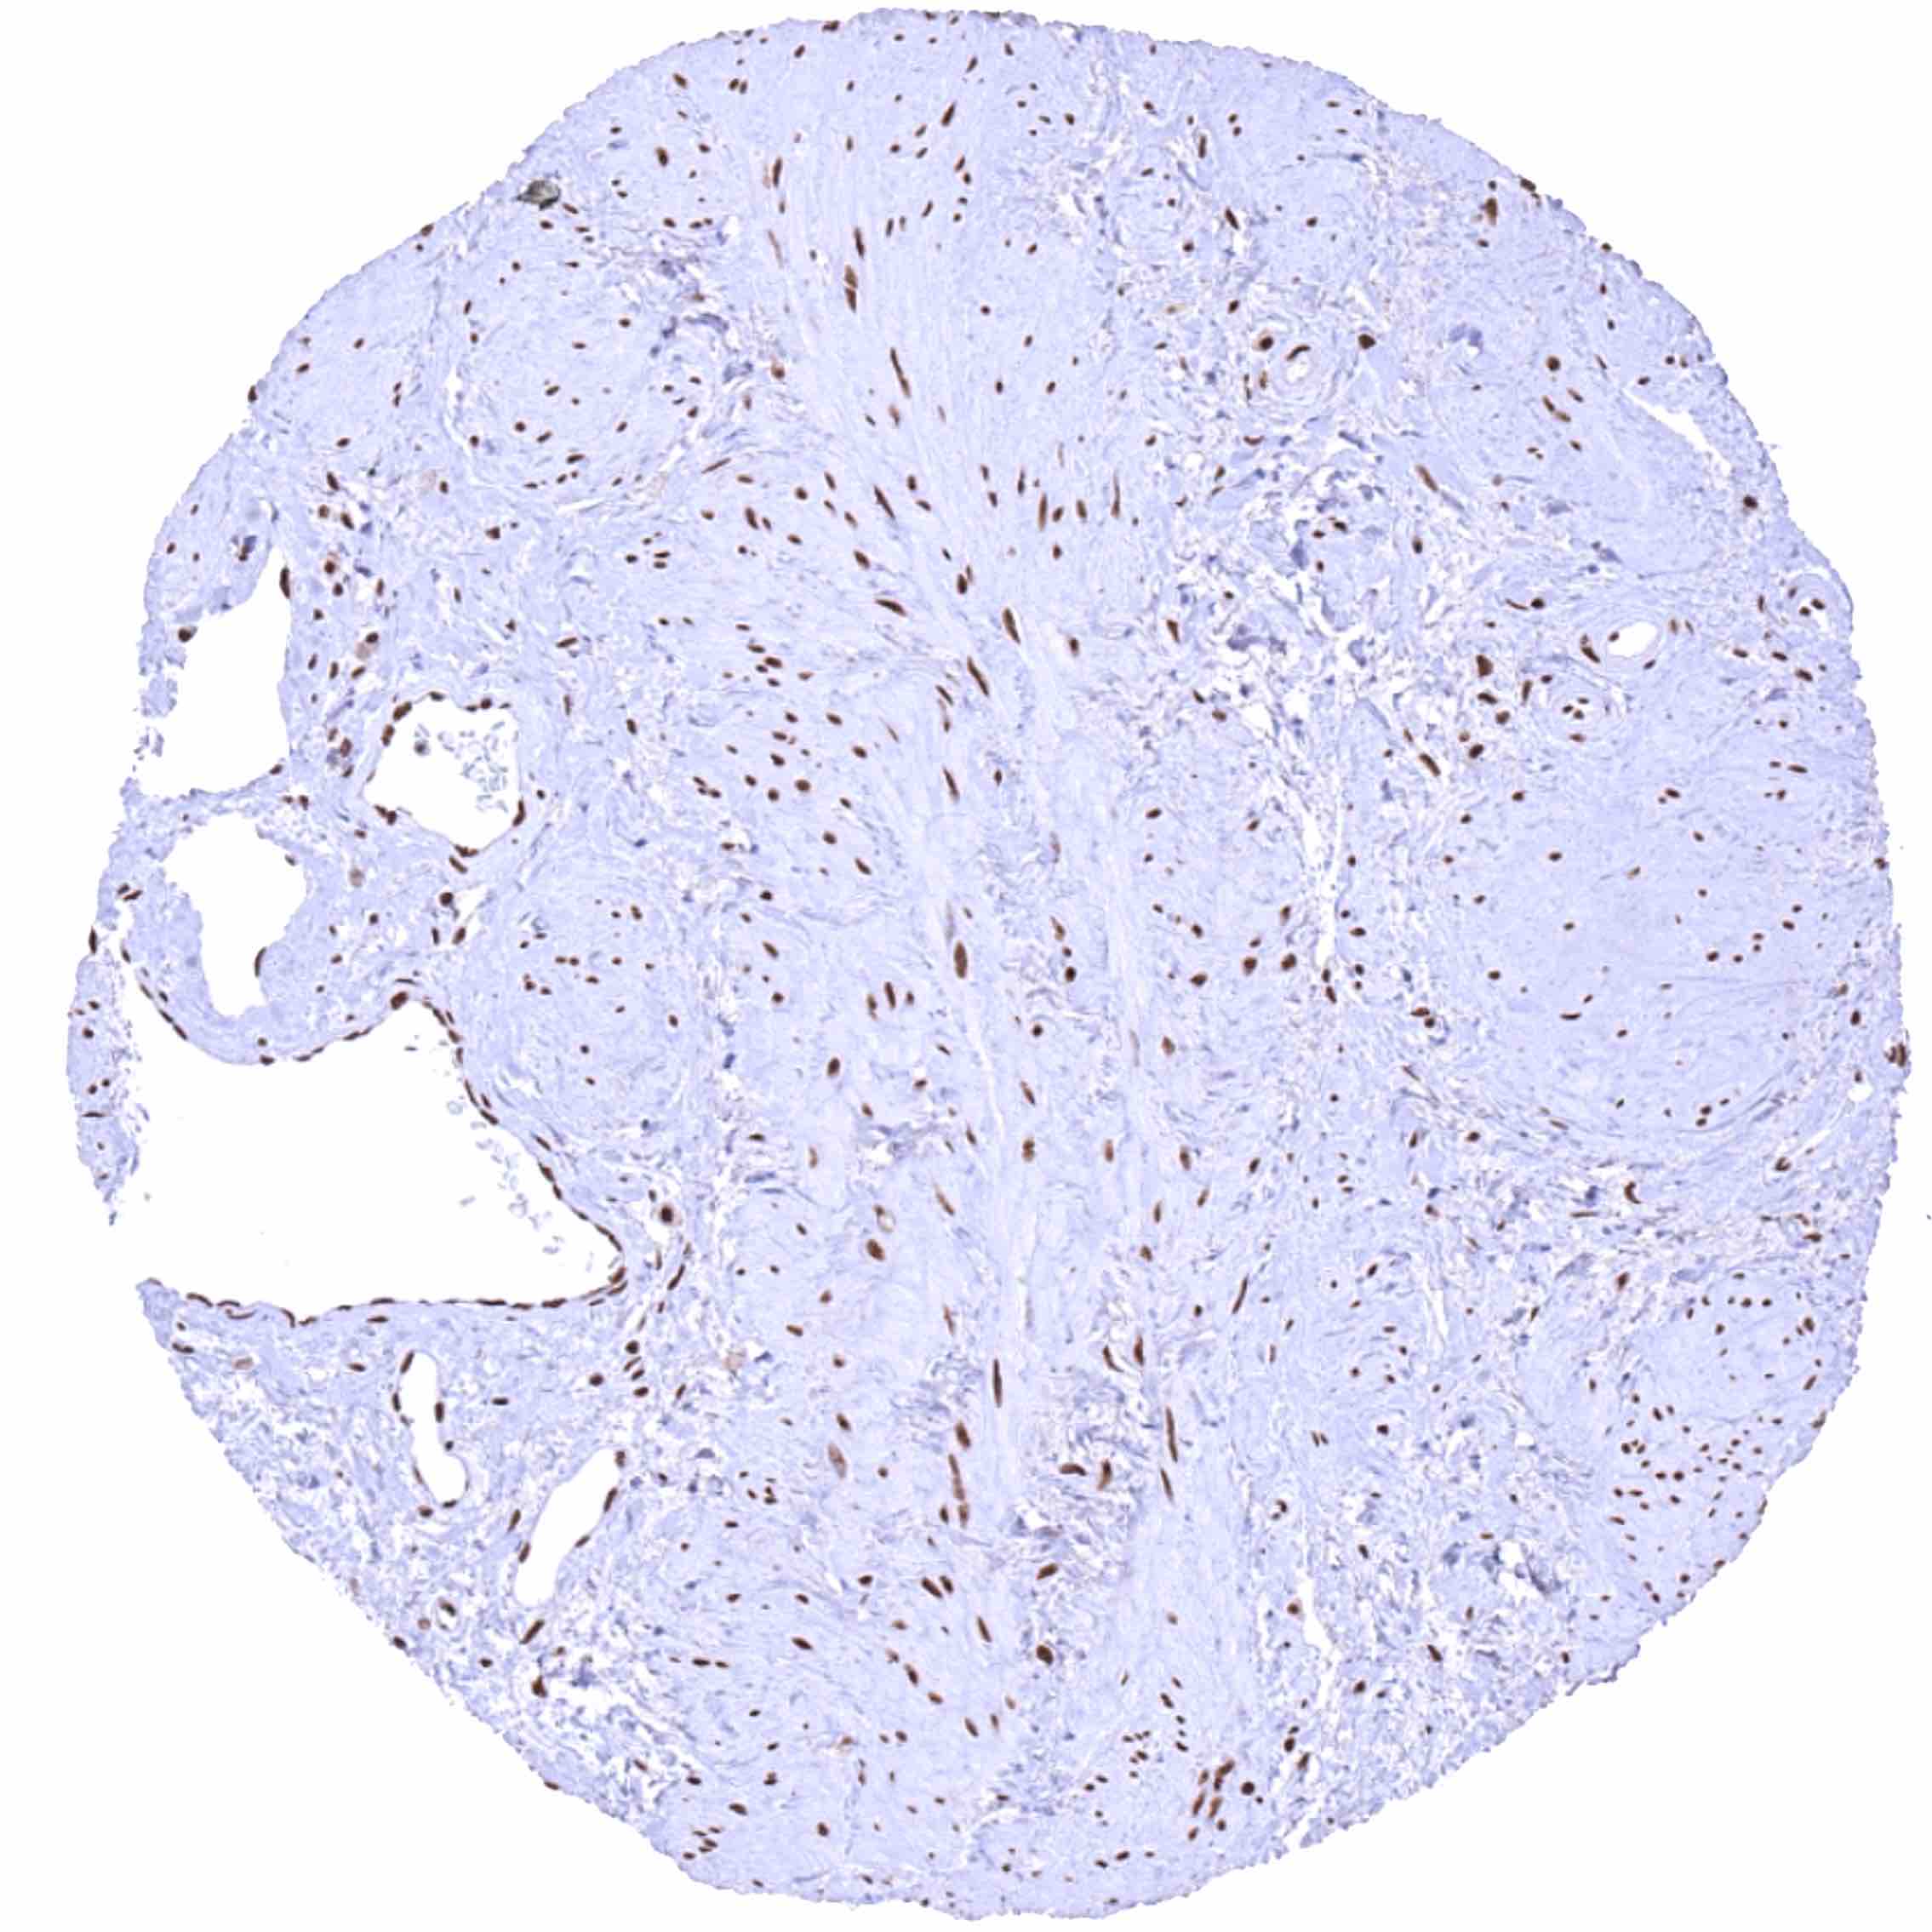

BRD4 antibody [HMV4275] HistoMAX™

Prostate – BRD4 staining of basal cells is somewhat stronger than of acinar cells.